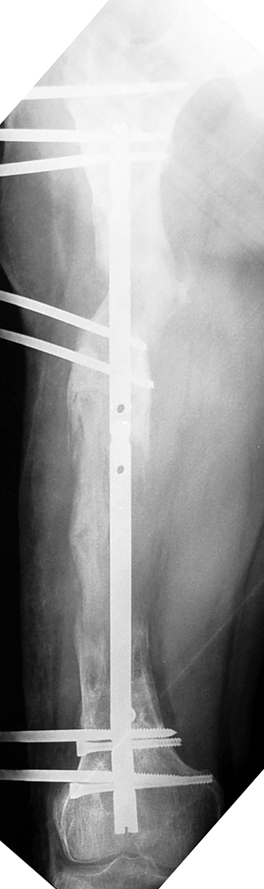

Appropriate radical debridement necessitates excision of all necrotic bone and soft tissues, and frequently causes instability at the involved extremity. The remaining bone and soft tissue defect has to be fixed and reconstructed. The distraction osteogenesis method of Ilizarov is used successfully for achievement of union, correction of the deformity, elimination of limb length inequality and reconstruction of segmental bone defects.

The duration of external fixation (external fixation index) depends on the amount of distraction required, and the extremity is prone to complications during this period. After the distraction phase is completed, the external fixator remains in place during the consolidation phase, which lasts twice as long as the distraction phase; but this period is hardly tolerated. If the external fixator is removed before sufficient consolidation is achieved, fractures, deformity and shortness will be the result. In our department, ‘lenghthening over nail’ method is used in order to decrease the external fixation index and increase patient comfort and activity level. In this method, the intramedullary nail is statically locked after the completion of the distraction phase, and external fixator is removed. The extremity is stabilized by the intramedullary nail during consolidation phase. In this way, complications due to long external fixation index or early removal of the external fixator are avoided.

Case 3